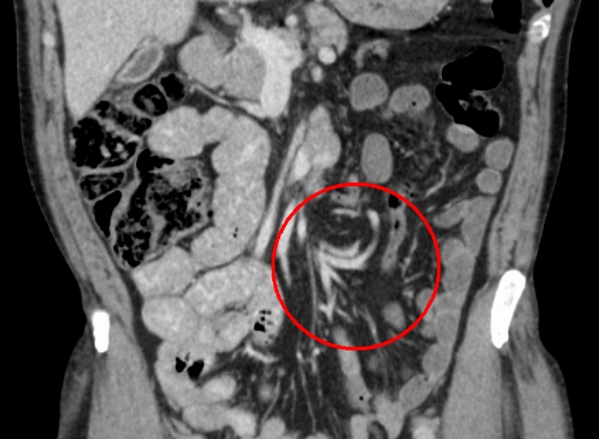

장꼬임 진단

심한 복통과 탈수 등으로 병원 진찰 등으로 진단받을 수 있습니다. 복부 X-ray와 내시경, CT등의 검사 방법이 있으므로 크게 걱정할 필요없이 장꼬임 증상 중 대표적인 복부통증 심하다 싶으면 병원을 찾으시는게 큰 고생 없이 넘길 수 있습니다.